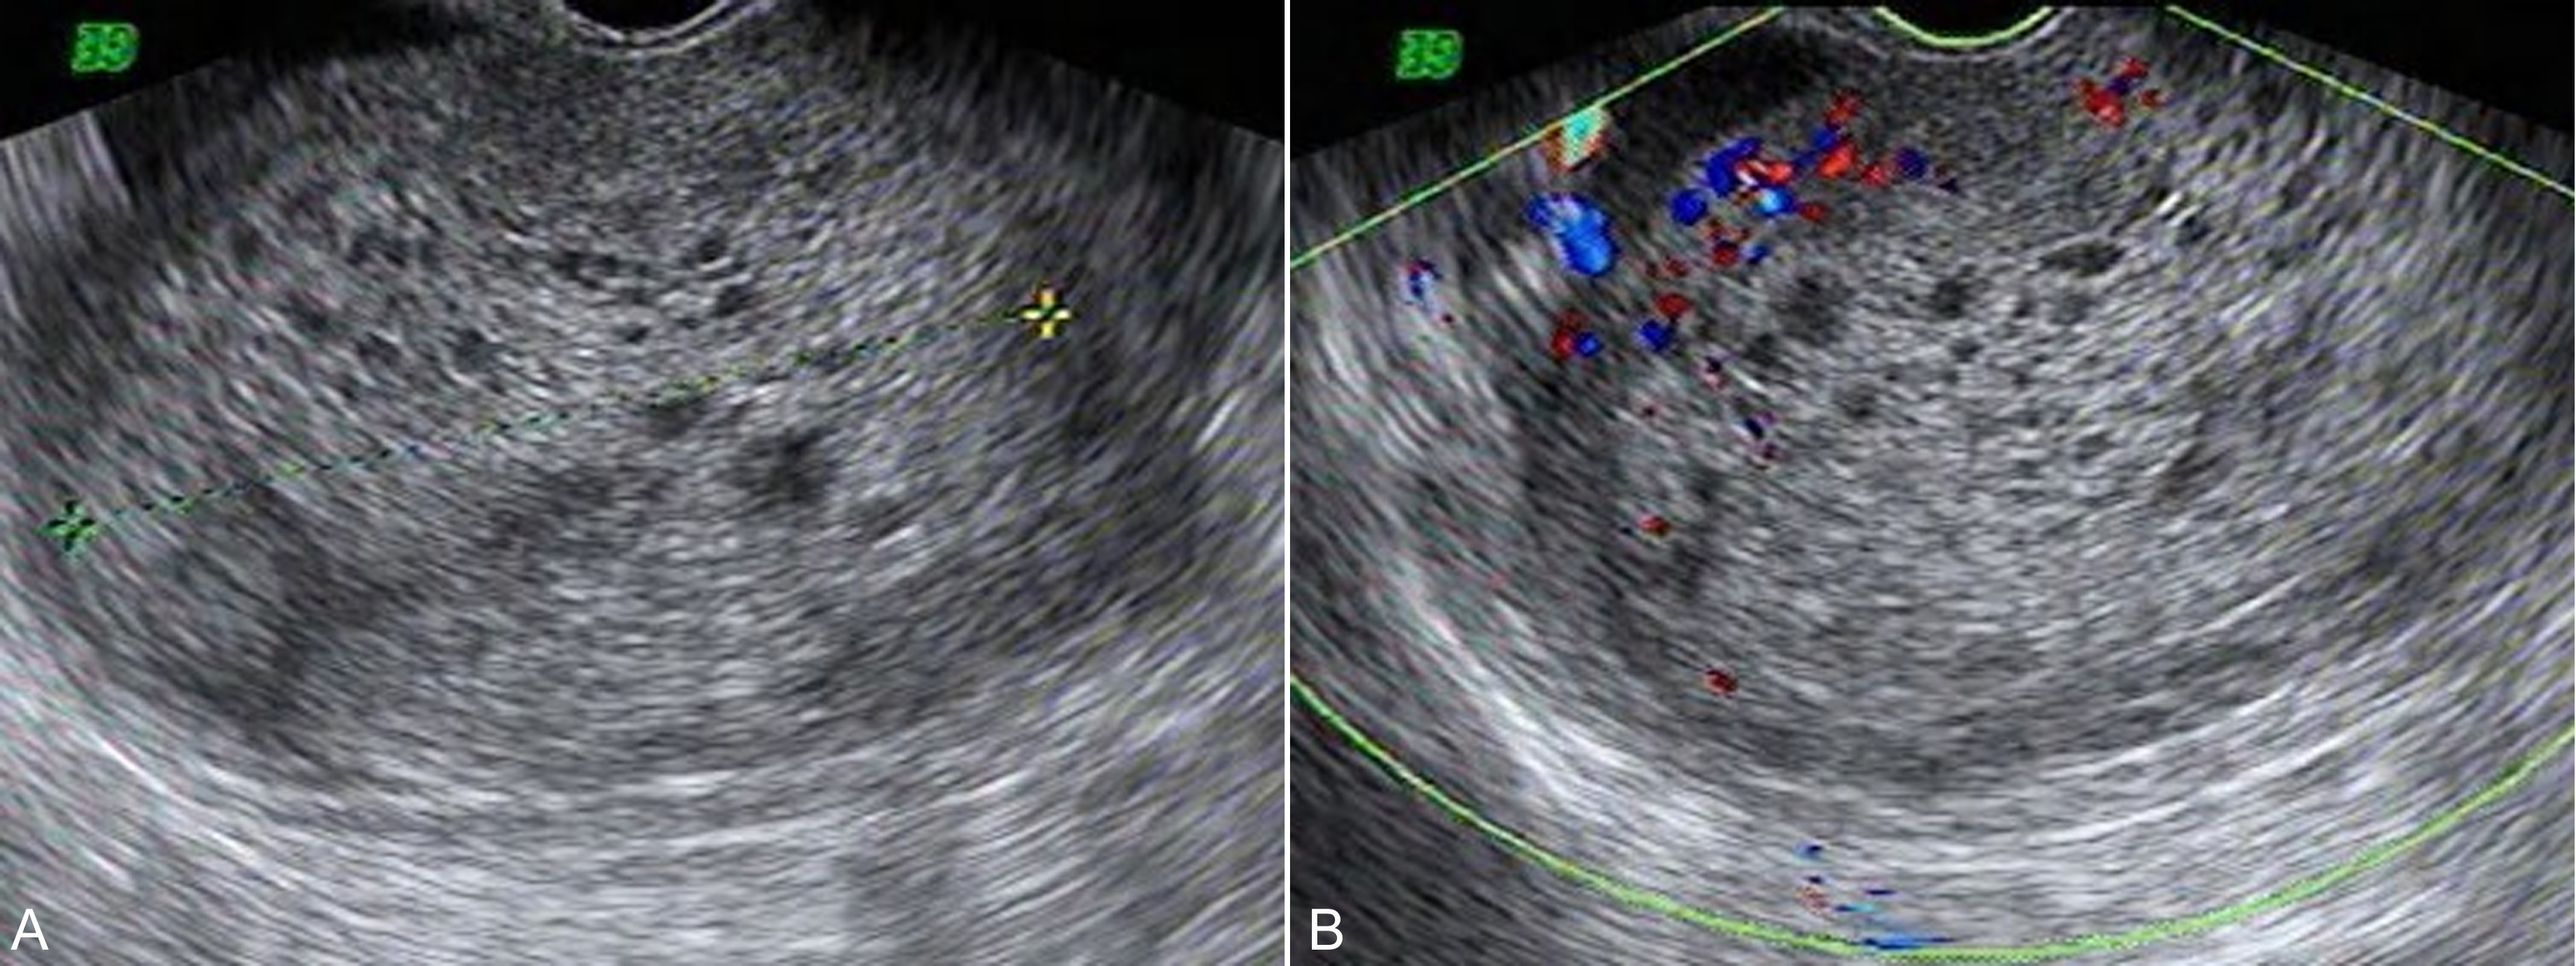

彩色多普勒血流显像检查可以发现子宫动脉及子宫壁血流明显加速,舒张期血流速度明显加快,形成典型的低阻力血流频谱(图4);随着治疗的好转局部血流逐渐减少,血流阻力逐渐升高恢复正常。以彩色多普勒能量图检查可以更为敏感地显示丰富的血流。经阴道彩色多普勒超声检查可以获得更好的图像分辨率和敏感的血流显示;三维超声检查可以重建子宫内病变的形态及其血管空间结构,对病变的评估复查更帮助。

图4葡萄胎水泡状组织周围及子宫壁血流增多及低阻力型血流速度曲线